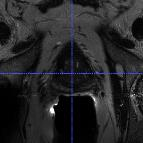

Prostate cancer biopsy benefits from accurate fusion of transrectal ultrasound (TRUS) and magnetic resonance (MR) images. In the past few years, convolutional neural networks (CNNs) have been proved powerful in extracting image features crucial for image registration. However, challenging applications and recent advances in computer vision suggest that CNNs are quite limited in its ability to understand spatial correspondence between features, a task in which the self-attention mechanism excels. This paper aims to develop a self-attention mechanism specifically for cross-modal image registration. Our proposed cross-modal attention block effectively maps each of the features in one volume to all features in the corresponding volume. Our experimental results demonstrate that a CNN network designed with the cross-modal attention block embedded outperforms an advanced CNN network 10 times of its size. We also incorporated visualization techniques to improve the interpretability of our network. The source code of our work is available at https://github.com/DIAL-RPI/Attention-Reg .